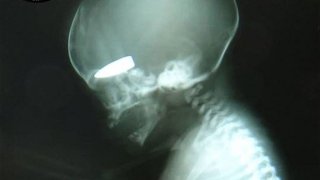

Британският хирург David Nott обяви, че снайперисти убивали бременни жени по улиците, срещу награда...